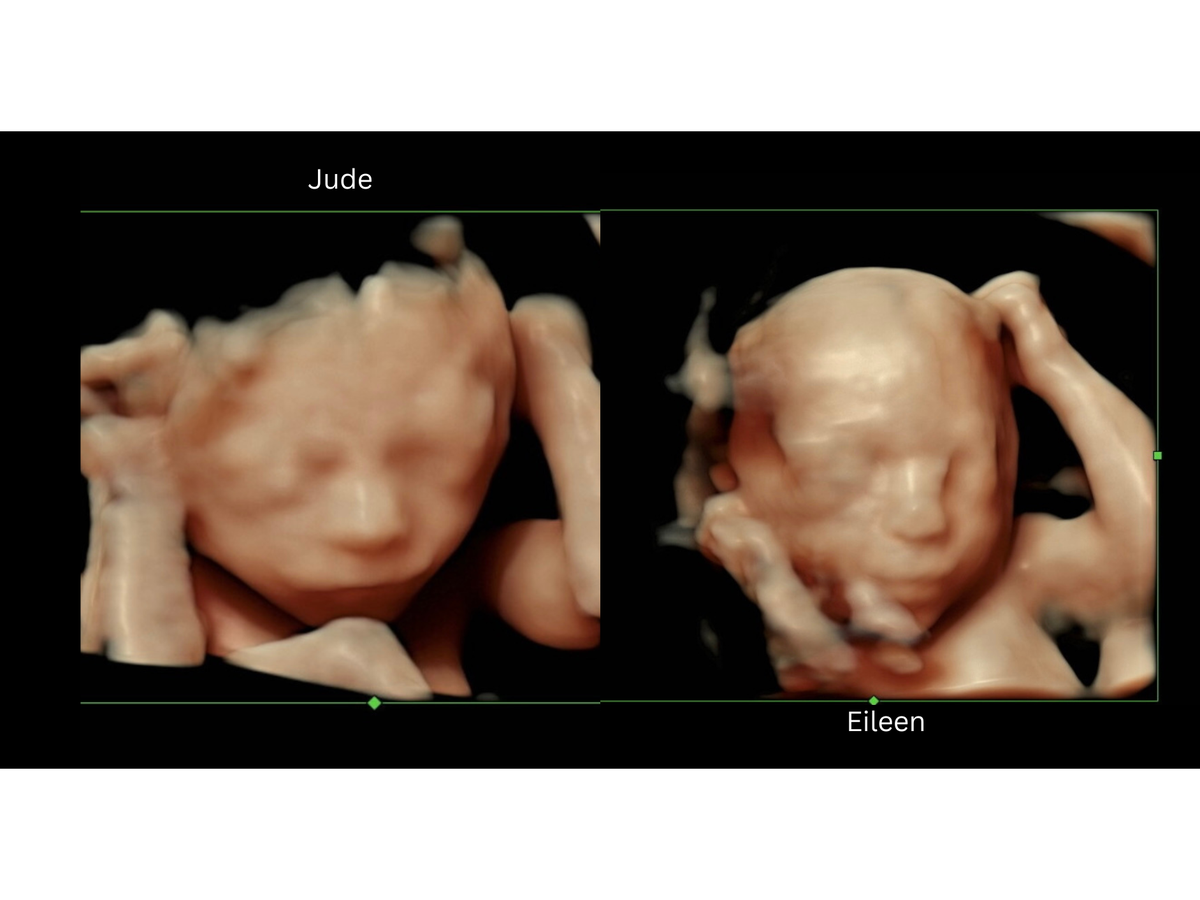

Our family was ecstatic to find in July that our sweet Ava was expecting and doubly excited to find out a few weeks later it was twins! We anticipated a smooth and healthy pregnancy but in September our hearts were shattered to learn of some major complications. The outlook was grim and the babies were given only a 10% chance of survival but against the advice of her doctors to terminate the pregnancy, Ava decided to pursue further testing to exhaust every ounce of hope for her babies. At 19 weeks we received the results and a miracle. Against all odds the babies were fighting for survival and they are succeeding! With that being said, Ava and both girls will need specialized medical care during the pregnancy and long after due to several incredibly rare conditions. On top being mo/di twins Baby B (Eileen) has been diagnosed with a congenital diaphragmatic hernia (CDH) — a serious condition where her stomach, intestines, and liver have moved into her chest, preventing her lungs from developing properly. She will need immediate surgery after birth and an undetermined amount of intensive care. Our Baby A (Jude) is also facing challenges with restricted blood flow due to an umbilical cord placement issue that is slowing her growth. Because of these complications, both of our twins will be born premature and will require specialized neonatal care.